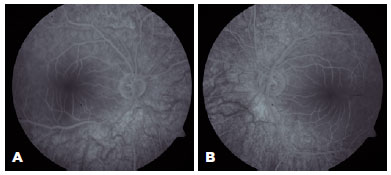

A 19-year-old female patient presented to our clinic with complaints of bilaterally decreased vision for the past 8 years. These complaints had been worsening within 5 years, which were thought to be fatigue, tremor, ataxia, and myoclonic epilepsy after simple daily activities. Her siblings had no history of neurological and ophthalmic diseases. Her best-corrected visual acuity was 20/125 on the right and 20/200 on the left. Slit-lamp examination revealed clear cornea in both eyes and multiple punctate opacities in both lenses. In the fundus examination, bilateral macular CRS was observed with its characteristic red fovea and pale macula (Figure 1). SD-OCT (Heidelberg Engineering, Heidelberg, Germany) imaging revealed hyperreflectivity of the inner retinal layers and increased hyperreflectivity on the photoreceptor layer in the foveola region (Figure 2). In the fundus fluorescein angiography (FFA), slight shading and mild hypofluorescence with a blurred appearance at the vessel borders were observed in the macula (Figure 3). The patient was referred to the neurology department, and various analyses were performed (Table 1).

FFA showed hypofluorescence in the macular region as a result of blockage due to substance accumulation in the ganglion cell layer. This area corresponded to the hyperfluorescent area in SD-OCT. Retinal artery occlusion is among the diseases that should be considered in the differential diagnosis of patients who present with macular CRS. The FFA result in our case was not compatible with retinal artery occlusion.